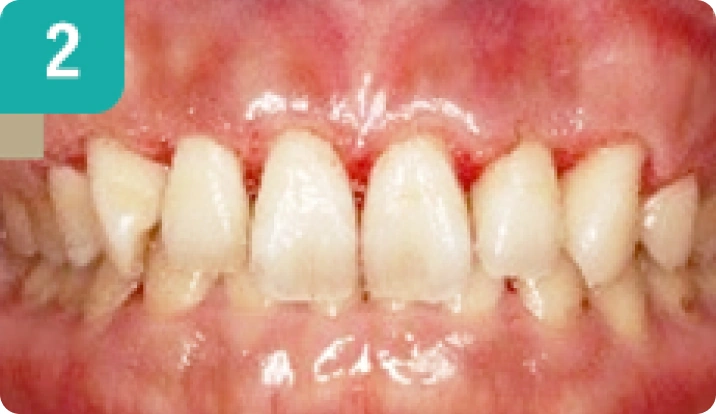

歯肉整形 8本

左右非対称なガミースマイルを歯肉整形(骨整形)にて改善しました。この症例は顎顔面の骨格的な歪みがあり、歯並びや咬み合わせも左右非対称です。骨切り手術を含めた大規模な矯正治療を検討しているとのことでしたが、いったんは比較的に低侵襲な選択肢として、歯肉整形(骨整形)とホワイトニングで審美的な改善を行いました。

【治療期間】3週間 【費用】80,000円(税別) 【リスク・副作用】術後2~5日程は傷口に赤みが見えたり、痛みが生じる場合があります。当院で行う歯肉整形は歯と歯肉、歯槽骨に対して行う処置であり、入院が必要な骨切り手術(Le Fort手術)などは対応していません。